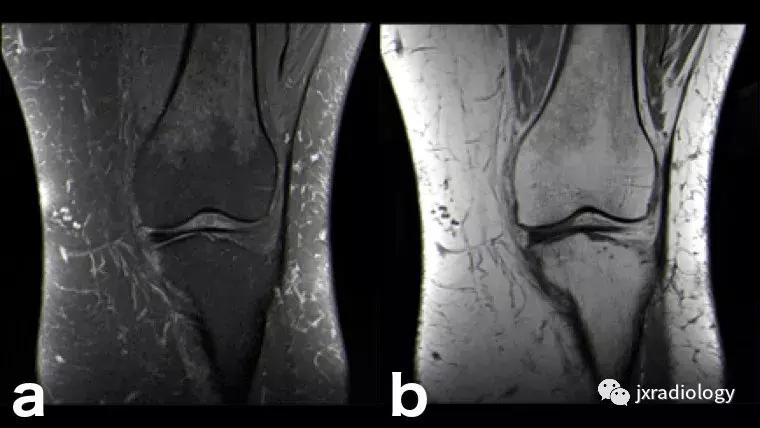

图28:正常的红骨髓:这是寻找骨髓水肿时可能出现的误区。 造血系统红骨髓(由于年轻患者正常分布或成人骨髓再生)在T1-WI(b)和水敏序列(a:PD-FS-WI)上均具有中等信号强度。 T1-WI上的正常红骨髓相对于肌肉的分布(通常在干骺端)的特征性模式和较高的信号强度(与T1-WI上肌肉组织的等信号或低信号的病理性骨髓相反),应能及时发现这一正常发现。